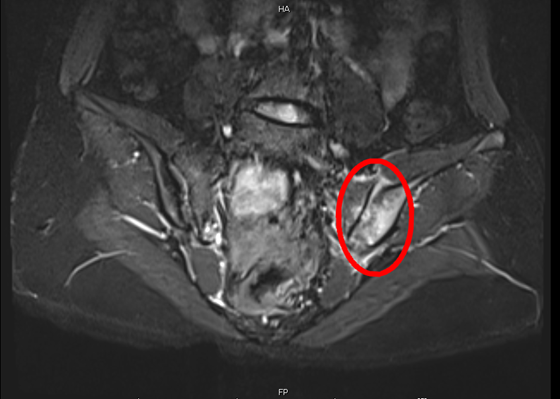

骶髂关节面下骨质内可见片状高信号灶明显强化